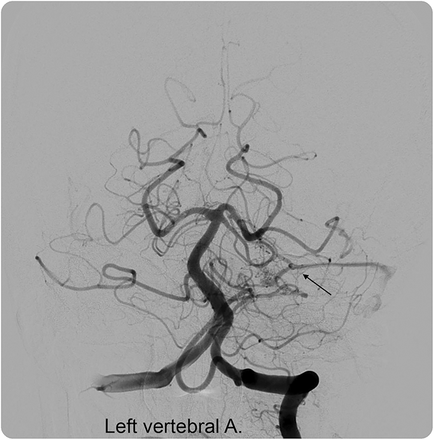

执行脑血管造影术和早期静脉引流动静脉瘘的建议,美联储前下小脑动脉,排入优越伪劣坚硬的鼻窦(图2)。

图2

脑血管造影,前后的视图,midarterial阶段,左椎动脉注入

脑血管造影前后的观点,midarterial阶段,左椎动脉注射显示早期静脉引流到上级坚硬的窦(箭头所指)。